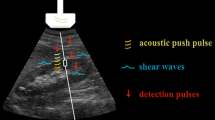

Analytical method

The principle used for analysis in this study was based on the acoustical structure qualification (ASQ) method developed by Yamaguchi et al. [11–14] for statistical analysis of the probability density function (PDF) of RF signal amplitude. The principle is briefly presented below.

A region of interest (ROI) is set within the liver parenchyma on the image taken, and the PDF is calculated for the RF signal amplitude within the ROI. Thus the calculated PDF is known to be approximated by the Rayleigh distribution if the ROI contains only speckle signals and is free of any tissue structure higher than the spatial resolution level [19]. If fibers increase as a result of progression of liver disease to chronic hepatitis or liver cirrhosis, PDF is considered to deviate from the Rayleigh distribution. With the conventional method of PDF analysis, however, only one ROI was set within the image. As a result, if the ROI contained large structures (e.g., blood vessels) even when containing no fibers, or if the echo signal intensity within the ROI was non-homogeneous because of the effect of attenuation, the PDF form tended to deviate from the Rayleigh distribution. To resolve these problems and to improve the precision of analysis, the ASQ method was specifically designed as follows. If the examiner sets a large ROI within the liver, hundreds of small ROIs are automatically set within the large ROI (Fig. 1). Then, PDF calculation and analysis of deviation from the Rayleigh distribution are carried out on each of these multiple small ROIs. The degree of deviation is calculated as the ratio of the actual RF signal variance to the mean variance for the multiple small ROIs. The degree of deviation is equal to 100% if PDF is consistent with the Rayleigh distribution. Such local analysis with small ROIs can reduce the variance in analytical results arising from attenuation or the presence of unnecessary structures (a problem with conventional methods of analysis) [14]. It is not affected by attenuation due to a thick abdominal wall (containing subcutaneous fat), because this method does not involve comparison of the signal amplitude itself but analyzes the ratio of variance. The manipulations and steps needed for this analysis are quite simple, and the results are not dependent on the examiner’s skill level.

Following this finding, we paid close attention to small ROIs showing marked deviation from the normal case (the theoretical Rayleigh distribution). To analyze the distribution of these small ROIs within the liver, we used computer program specifically developed for this purpose (making use of the above-mentioned principle of ASQ). With this program, the small ROIs showing a degree of deviation higher than the cut-off level were represented in red overlaid on B-mode images (Fig. 3). In this study, the diameter of each small ROI was set at about 1 mm, approximately equal to the liver nodule level, and the cut-off level was set at 200%. The red scatter thus obtained on B-mode images was called “US-Red”.